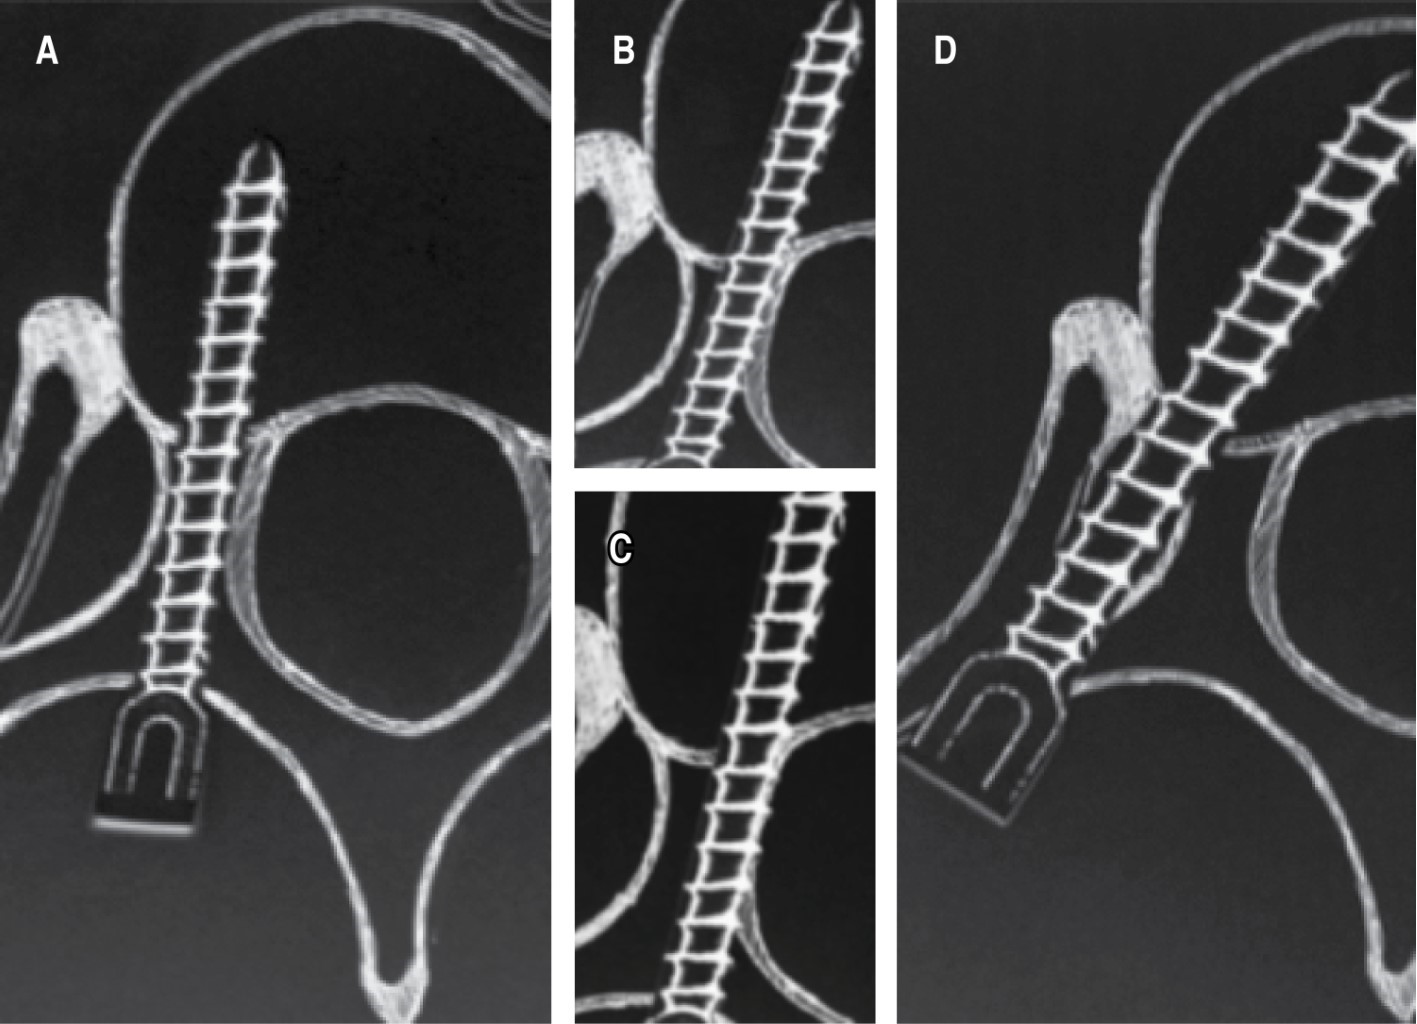

Figure 2